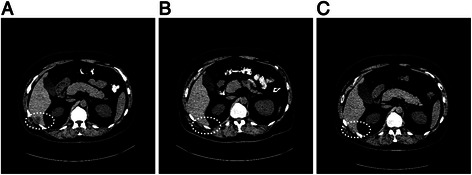

NRAS mutations (Q61R and Q61K in codon 61) were detected in two of ten patients (20%). One patient (case #4) attained a PR (TTF = 11.2 months) and had an NRAS mutation on NGS analysis from tissue taken from a continuously progressing lesion 6 months after treatment initiation; adequate tissue sample for testing before treatment was not available. The other patient achieved a CR (case #8; TTF = 5.6 months) and had an NRAS mutation detected in a single PCR assay from a biopsy of the solitary hepatic lesion that progressed after a brief period of initial response (3.8 months after treatment initiation; Figure 3), while the pre-treatment NGS analysis on this patient failed to show an NRAS mutation (17 months before treatment).

Figure 3.

Computed tomography scans. A) at baseline, B) 2 months, and, C) 3.8 months after treatment initiation with a combination of a MEK and BRAF inhibitor, of a patient (case #8) with short-lived CR (TTF = 5.6 months), who demonstrated an NRAS mutation in a biopsy obtained 3.8 months after treatment initiation. At 2 months, the liver lesion has regressed; at 3.8 months it recurred.